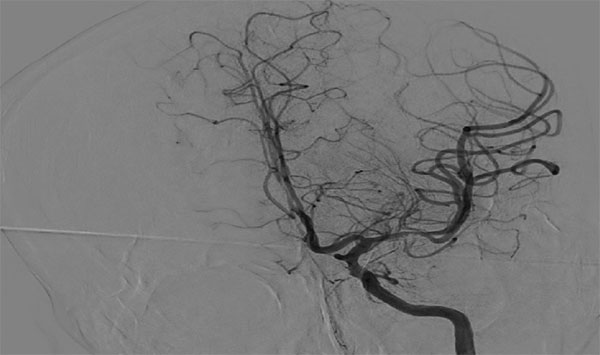

造影评估:急性左侧大脑中动脉闭塞

图1

图2